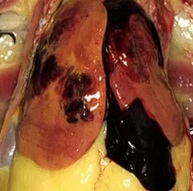

La suplementación con IGUSafe se asocia a una coloración más intensa y tejido firme, en contraste con los signos de esteatosis observados en el grupo control alimentado con dieta alta en energía.

Figura 2. Efecto de IGUSafe sobre la salud hepática en ponedoras y la reducción visible de los signos de hígado graso durante durante la fase tardía de postura.